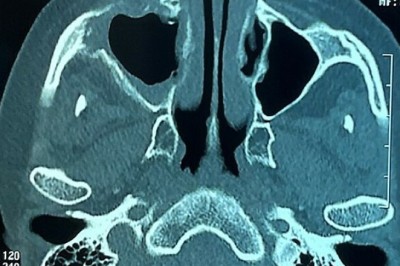

Tìm nguyên nhân nhiều người hoại tử sọ, hàm mặt sau mắc Covid

Sở Y tế TP HCM nhận định nhiều người bất ngờ bị hoại tử xương sọ, hàm mặt sau mắc Covid-19 là "vấn đề mới", yêu cầu các bệnh viện khảo sát và tìm hiểu nguyên nhân.